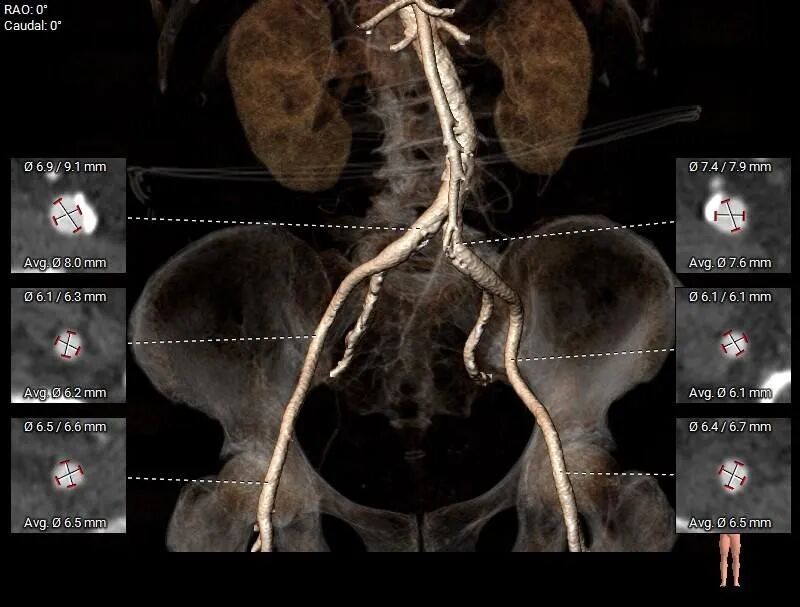

• 股-髂动脉走行适宜,内径可,腹主-髂总较多钙化分布。

股动脉入路

• 股-髂动脉走行适宜,内径可,腹主-髂总较多钙化分布,股动脉穿刺点位置附近无钙化,选择右侧股动脉作为主入路。